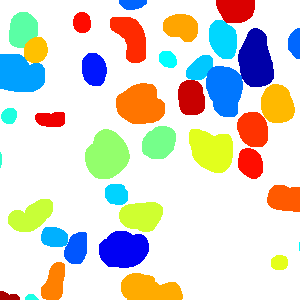

Figure 6 shows how our method segments the nuclei step by step. The color variety is well controlled by the color normalization procedure. The prediction result shows clear nuclear areas and nucleus boundaries. In the final segmentation result and ground truth image, each nucleus is represented by a different color.